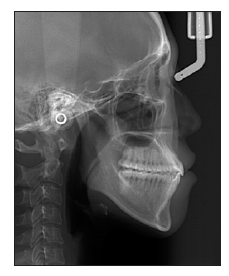

图 19

治疗后头侧位片"